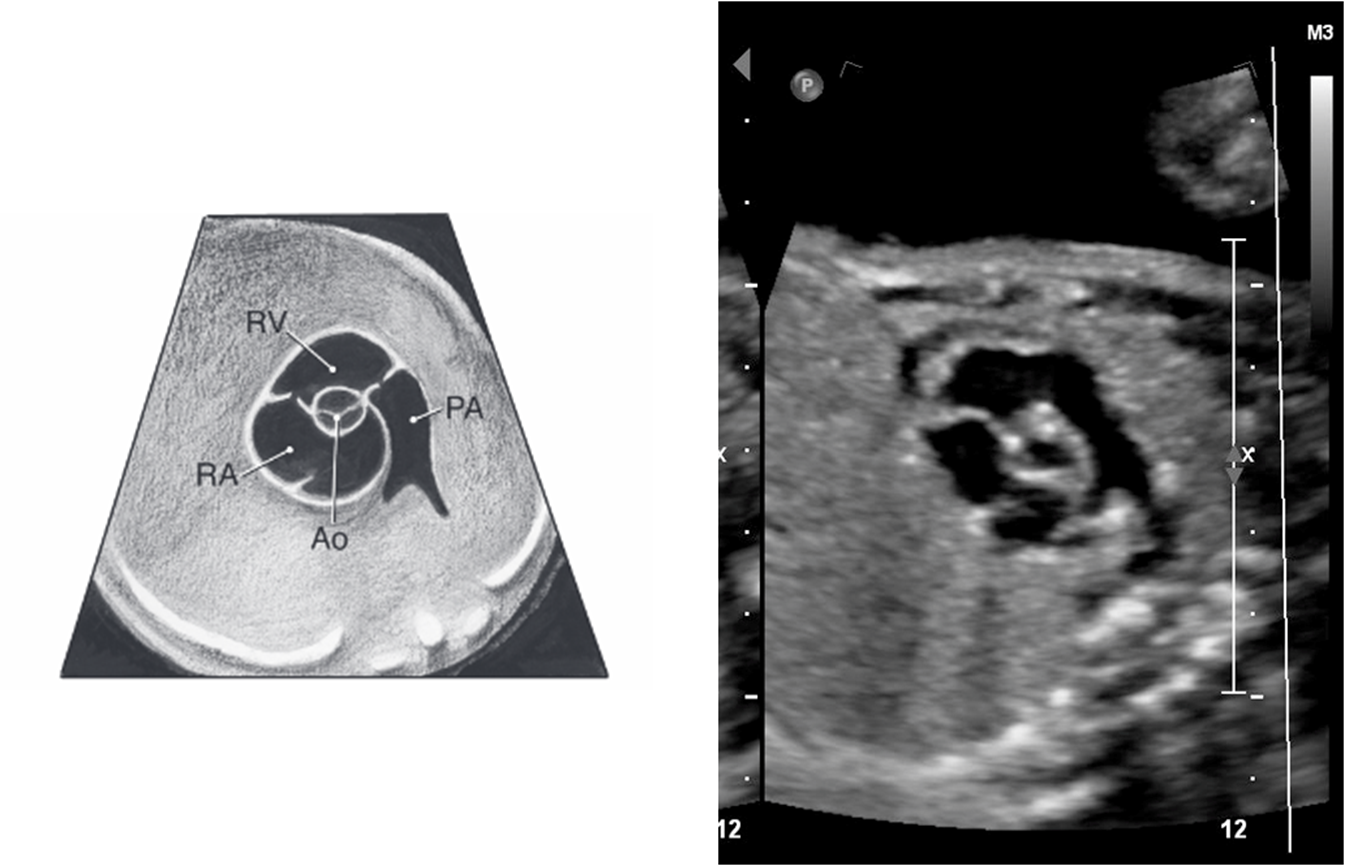

pulmonary artery comes out of ???

right ventricle

pulmonary artery quickly passes _____ and ____ of ascending aorta

anterior and left

right pulmonary artery passes ____ to the aorta

posterior

what does pulmonary artery split into

right and left pulmonary artery and ductus arteriosus

right pulmonary artery goes _____ aorta

behind

MPA always ____ or ____ ____ than aorta

equal or slightly bigger

RVOT

LVOT

3 vessel view (3VV)

pulmonary artery and aorta junction

ductus arteriosus

Where pulmonary artery and aorta join (ductus arteriosus) in the 3VT view is sometimes also referred to as the

transverse arches

3vt (thymus)

pulmonary artery vs aorta color flow

same color and flow towards spine